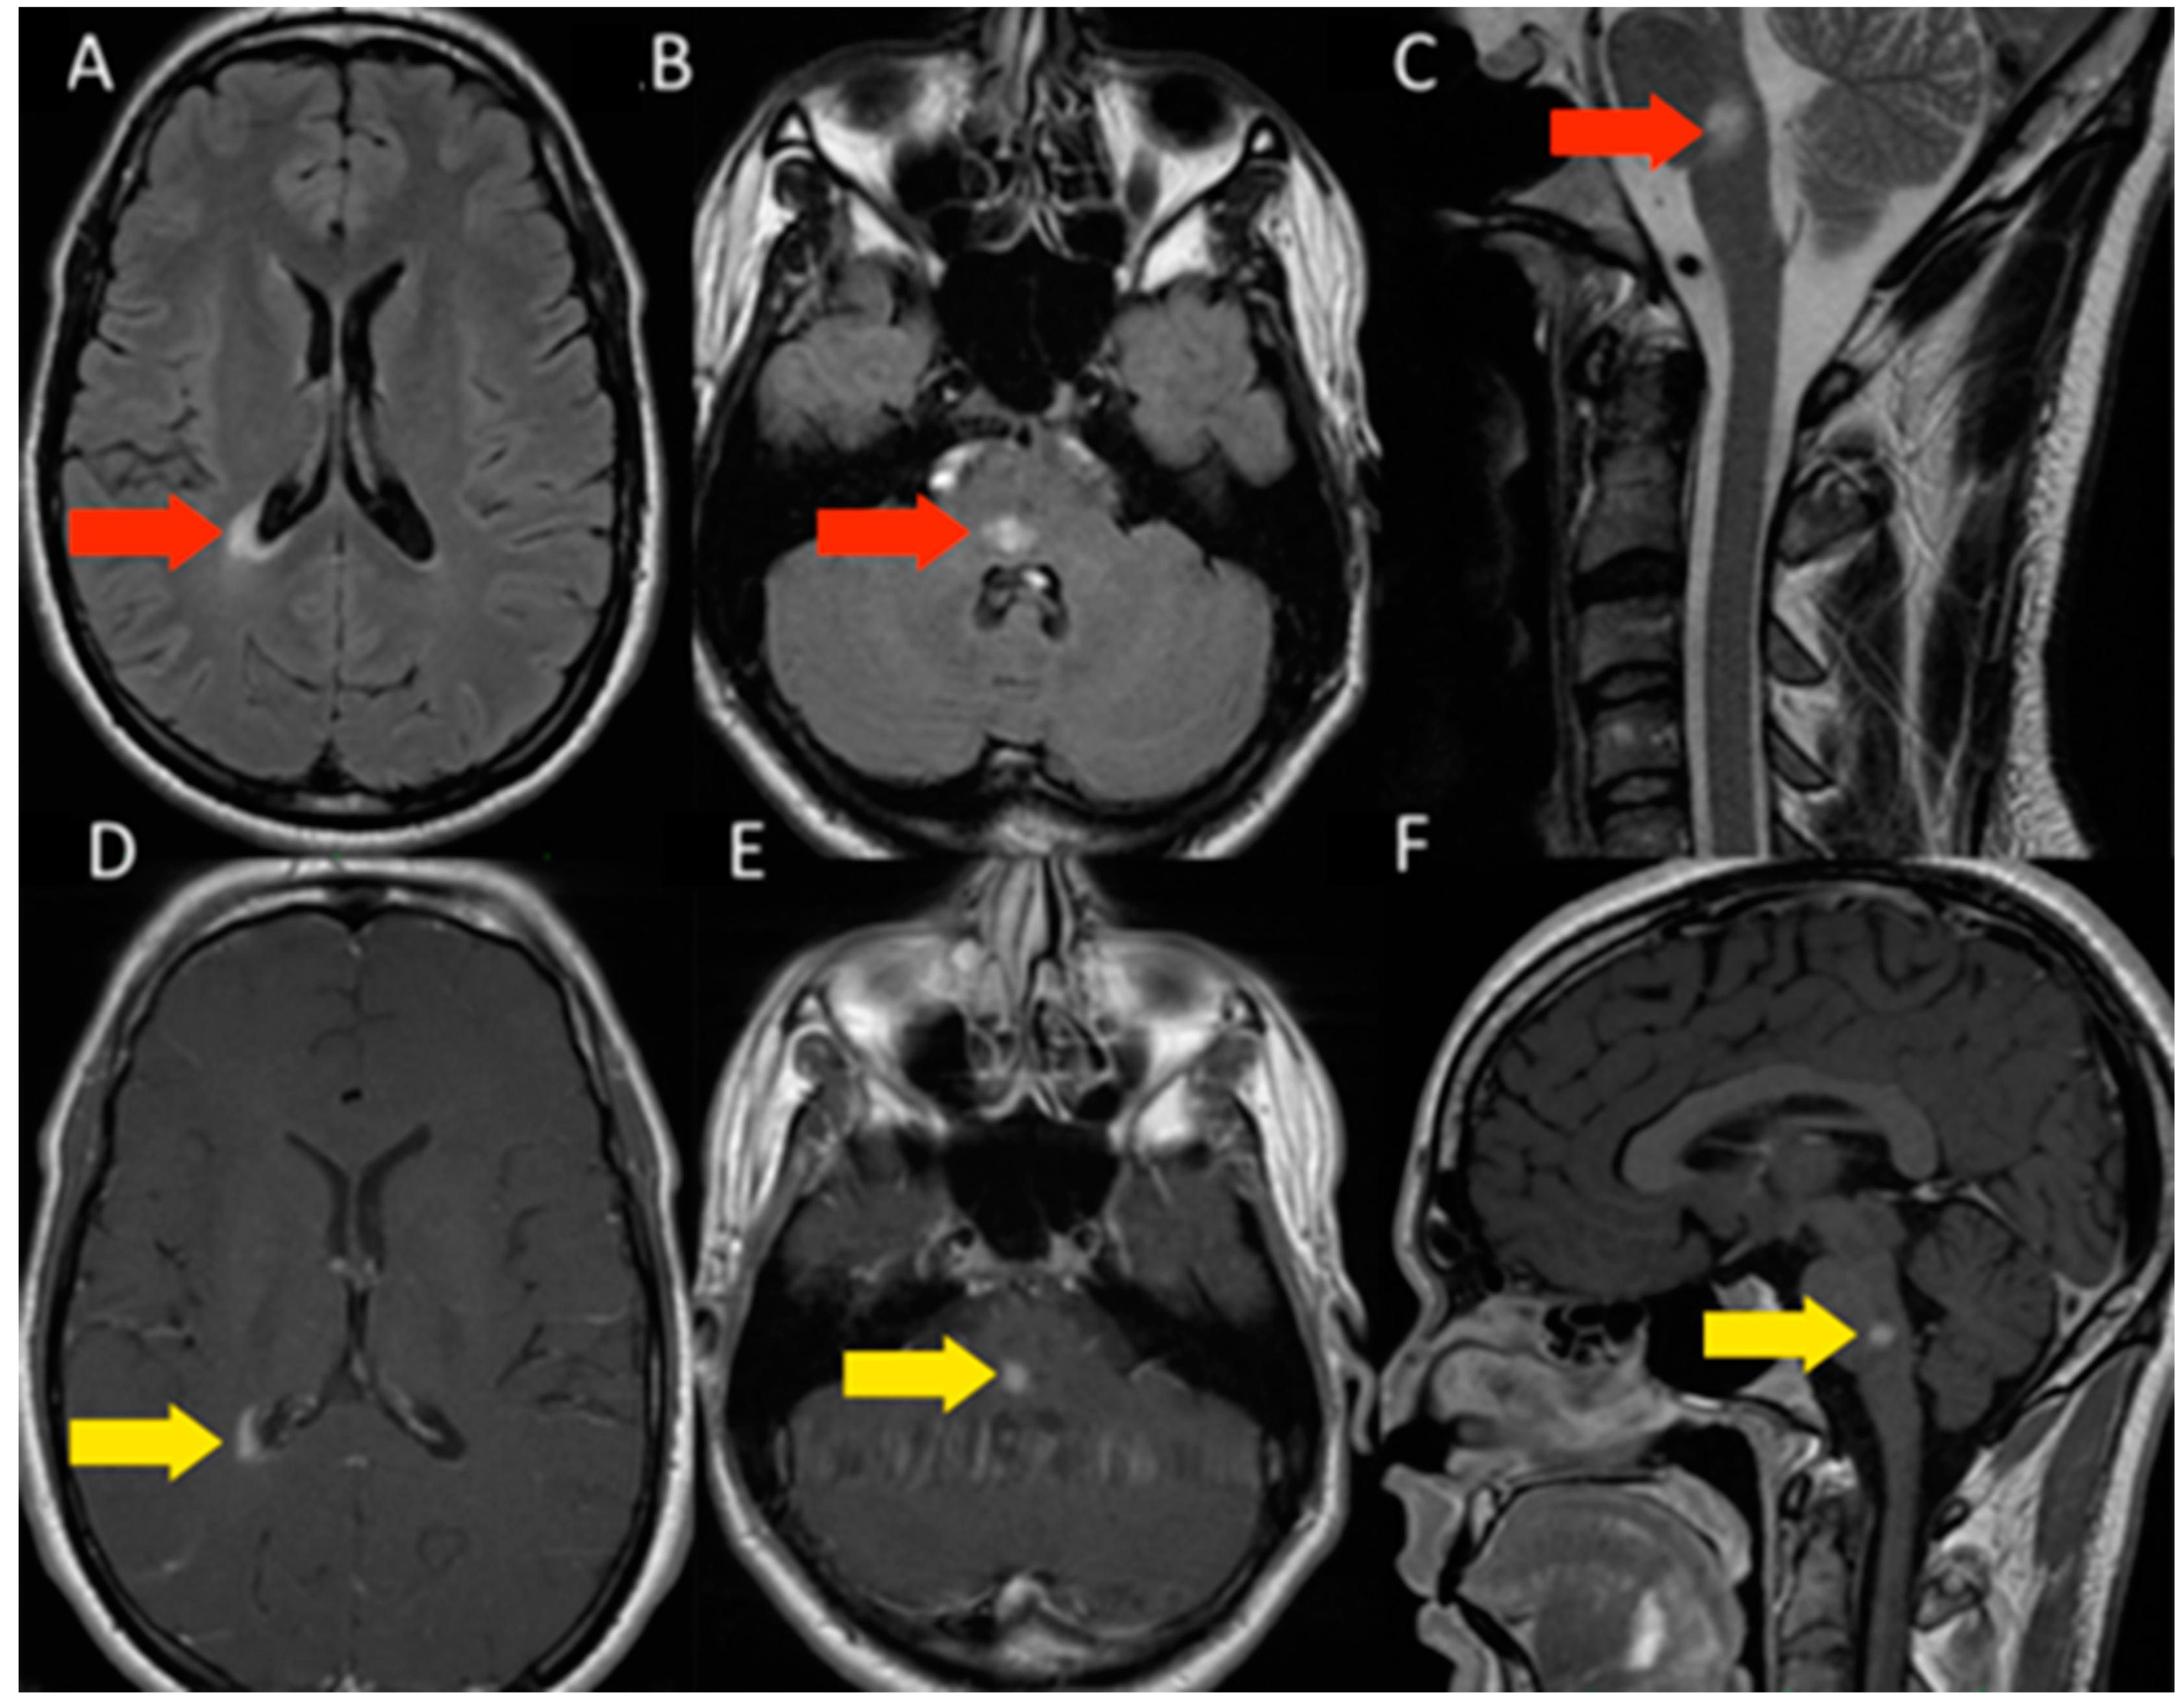

3.1.1. Patient 1